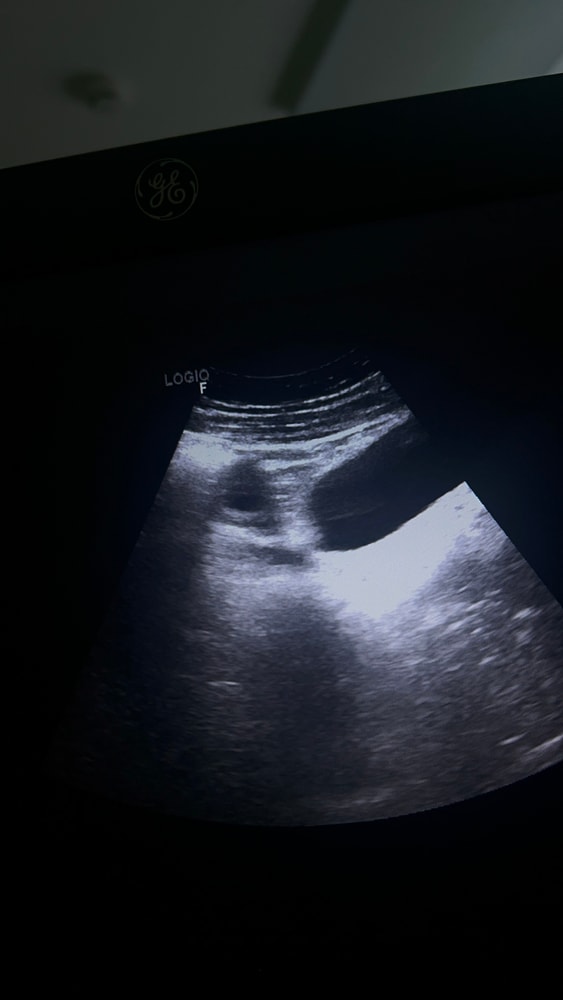

На обоих снимках вроде как яичники с фолликулами. Чтоб увидеть ЖТ надо смотреть кровообращение. Если есть круговое, то это ЖТ. По этому по этим снимкам не определить, увы